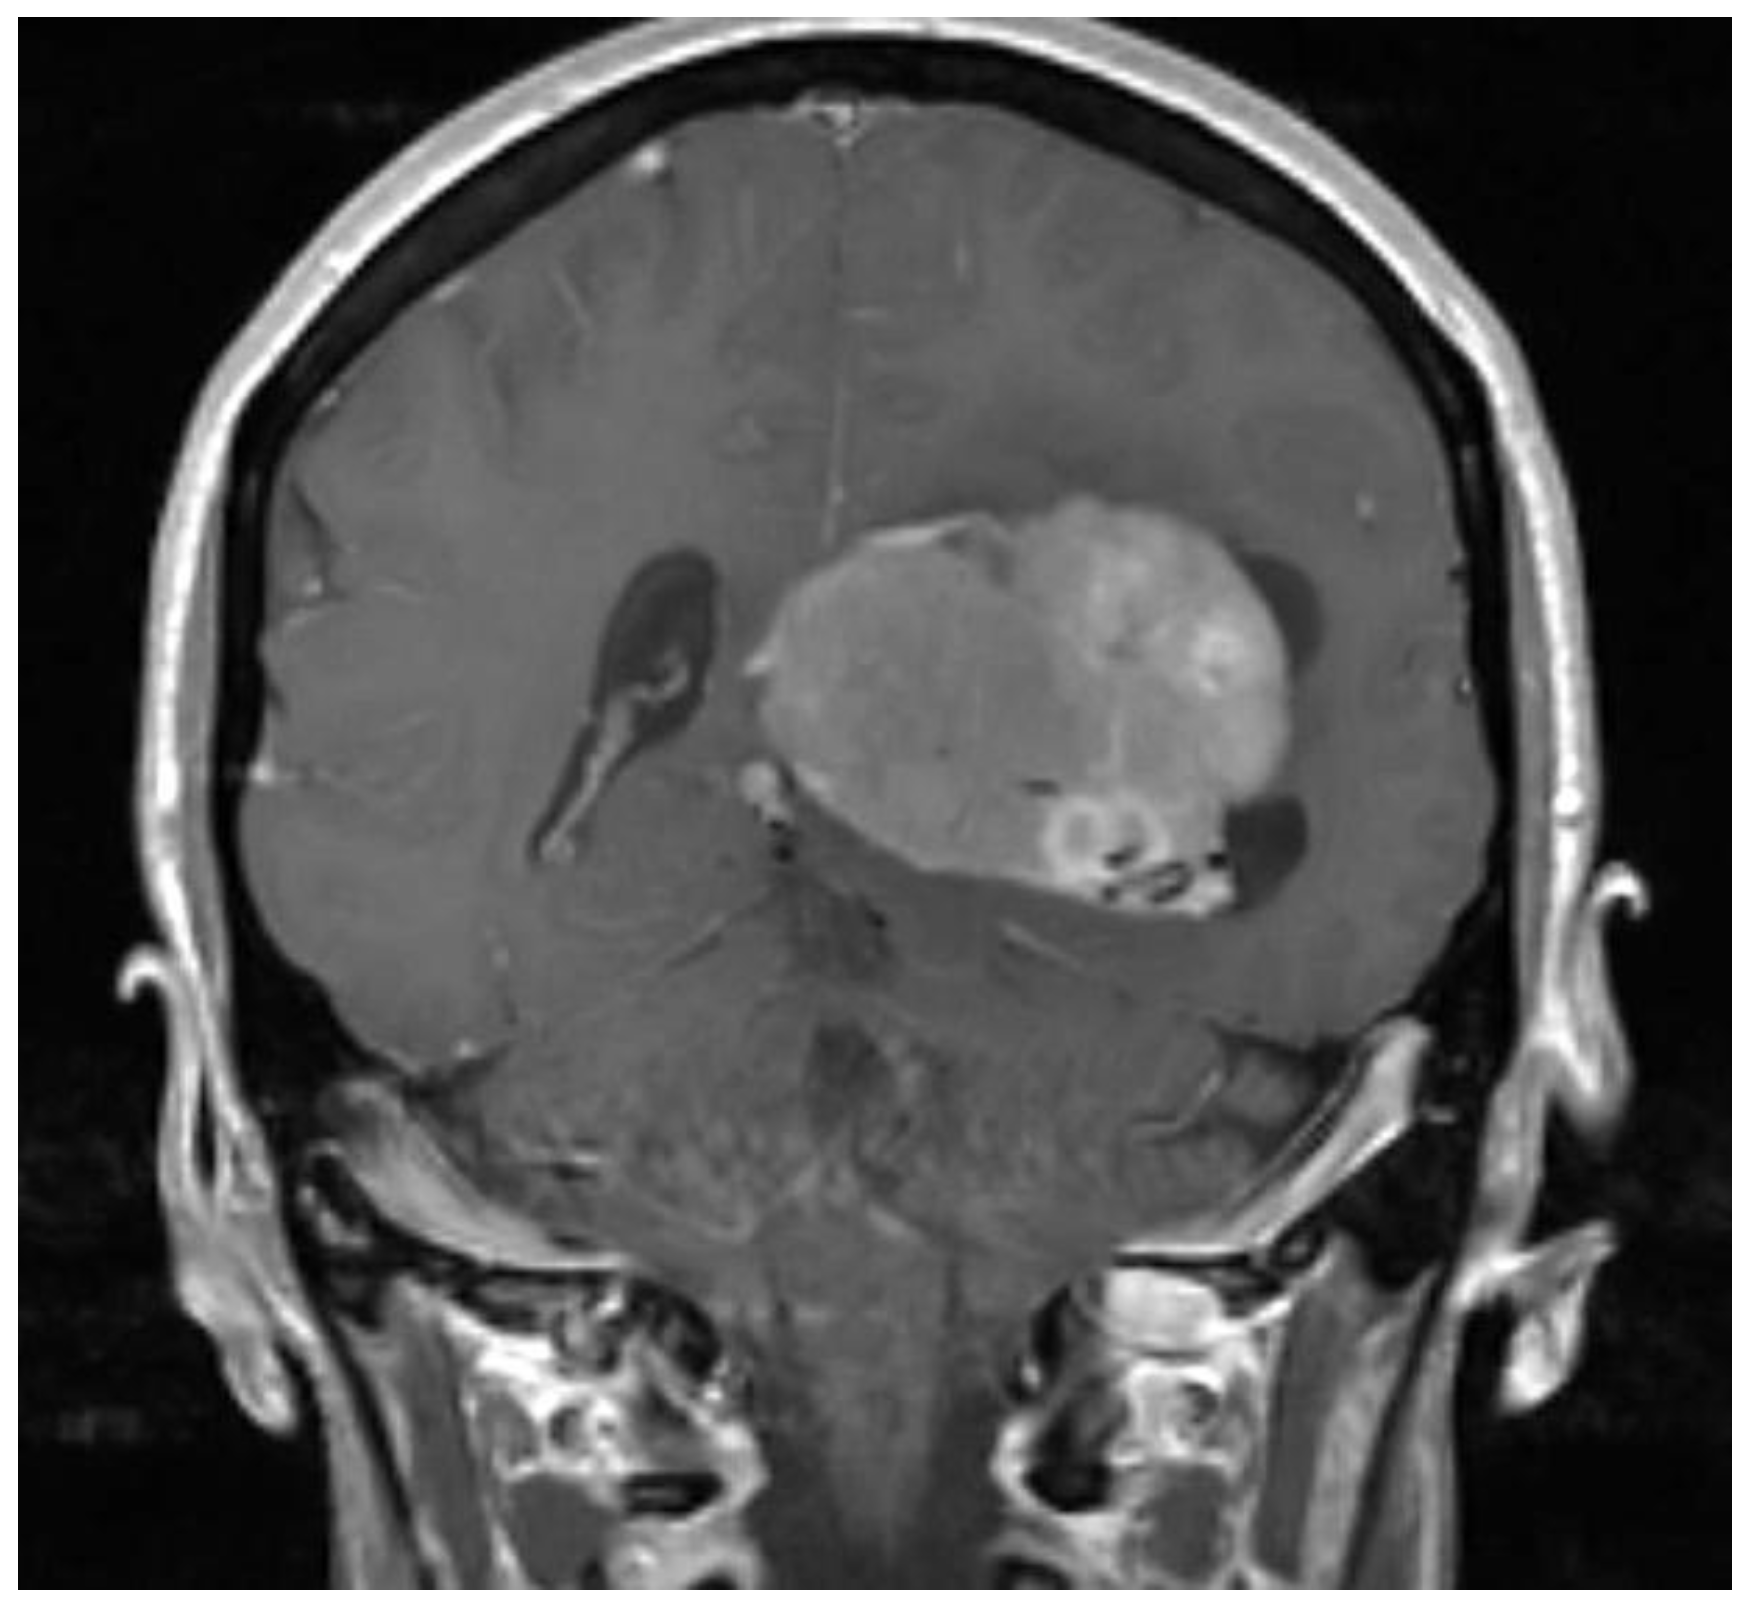

2. Case Presentation